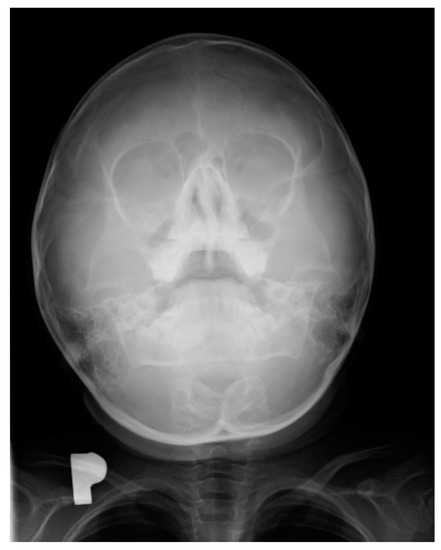

Pharyngeal cough occurred mainly during the day and was a major concern for the parents. Combined with a runny nose, it led to a suspicion of chronic sinusitis. In this period, an X-ray examination of the paranasal sinuses was performed in approximately 35% of the children. In turn, X-ray of the sinuses showed local thickening of the mucosa; no other pathological changes were revealed. The right sinus was larger than the left sinus, but the difference was not of clinical significance (Figure 2).

Figure 2.

X-ray of the sinuses of a 6-year-old girl.

In the course of teething, the tenderness and soreness of the mucosa cause infants to put their fingers and other objects in their mouth, stimulating saliva secretion. We observed that in older children, tooth eruption was accompanied by biting, gnawing, touching a sore spot with the tongue, or earache. Depending on whether the tooth emerged from the alveolar process of the mandibular or the jawbone, other symptoms also appeared. The most common were a cough and a runny nose, which are chronic in nature. They began in the moment the mucosa was pierced by the crown of a permanent tooth and increased in intensity until half of the crown had erupted. These symptoms gradually disappeared in the later stages of the tooth eruption. We observed clear differences in the type of cough associated with tooth eruption, depending on the type of teeth, the upper teeth being accompanied by pharyngeal cough, and the lower teeth by bronchial cough. Laboratory tests performed in the children during this period, such as complete blood count and C-reactive protein level, were normal. As for diagnostic imaging, sinus X-rays showed a slight thickening of the mucosa, while lung X-rays showed no focal lesions. Pharyngeal cough occurred mainly during the day and was a major concern for the parents. Combined with a runny nose, it led to a suspicion of chronic sinusitis. In this period, X-ray examination of the paranasal sinuses was performed in approximately 35% of the children, but apart from some local thickening of the mucosa, no pathological changes were revealed (Figure 1 and Figure 2). Nevertheless, approximately 25% of the children were referred for ENT consultations, and half of them were treated for chronic nonspecific sinusitis, often with antibiotics or nasal irrigation, with no significant improvement.